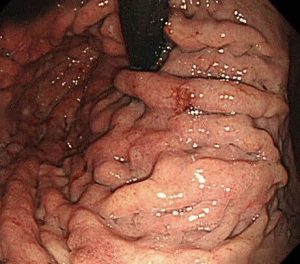

レントゲンで言われたように、胃の上部のひだが肥厚して腫れあがっています。

胃の壁は硬くなっていて、スコープで空気を入れてもこれ以上は広がりません。

これは「スキルス胃がん」です。

胃の粘膜下を這うようにしてがんが全体に進行するために、胃の壁が硬くなり広がらなくなります。

胃の上部から真ん中・出口近くまで、がんが粘膜下を這っています。